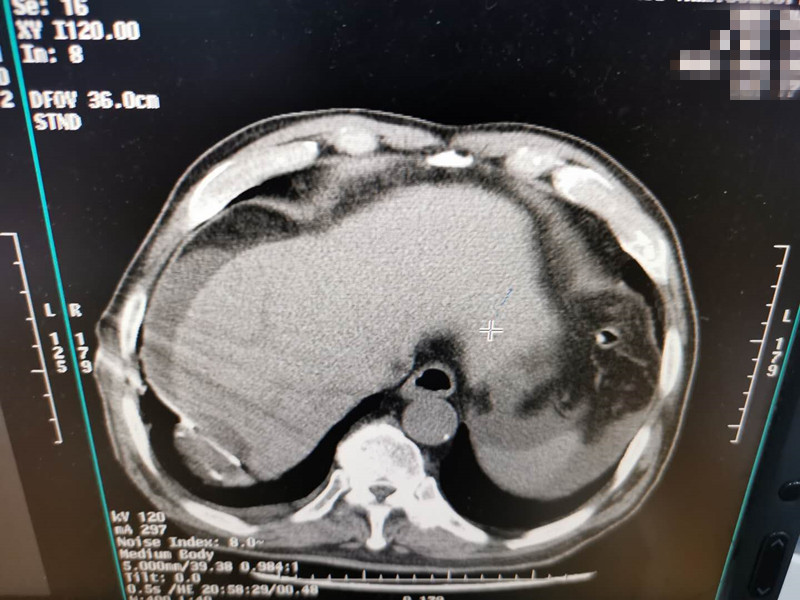

83岁肺部氩氦刀冷冻消融